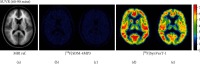

[18F]SynVesT-1 is a PET radiopharmaceutical that binds to the synaptic vesicle protein 2A (SV2A) and serves as a biomarker of synaptic density with widespread clinical research applications in psychiatry and neurodegeneration. The initial goal of this study was to concurrently conduct PET imaging studies with [18F]SynVesT-1 at our laboratories. However, the data in the first two human PET studies had anomalous biodistribution despite the injected product meeting all specifications during the prerelease quality control protocols. Further investigation, including imaging in rats as well as proton and carbon 2D-NMR spectroscopic studies, led to the discovery that a derivative of the precursor had been received from the manufacturer. Hence, we report our investigation and the first-in-human study of [18F]SDM-4MP3, a structural variant of [18F]SynVesT-1, which does not have the requisite characteristics as a PET radiopharmaceutical for imaging SV2A in the central nervous system.